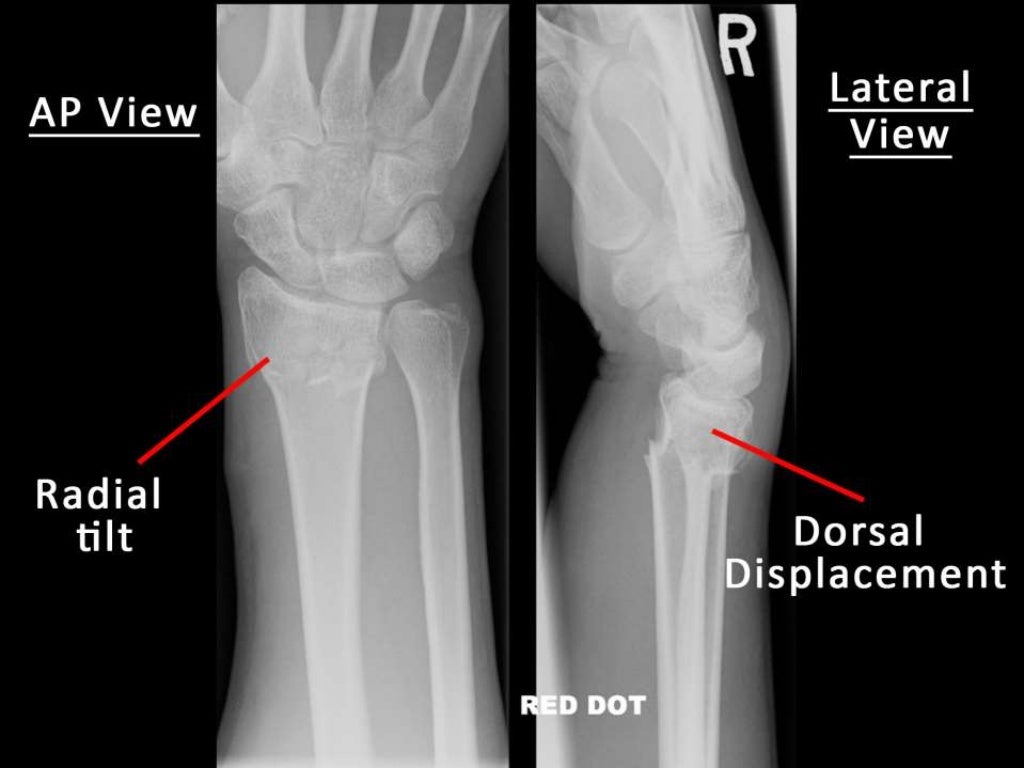

Radius End Fracture Ppt . this document provides information on fractures of the distal end of the radius bone. distal end radius fracture. The document discusses fractures of the distal radius. this document provides information on distal radius fractures. distal radius fractures are the most common orthopaedic injury and generally result from fall on an outstretched hand. It is the most common of. it is a transverse fracture of the distal end of the radius with posterior displacement of the distal fragment. They typically occur due to falls in older populations and. distal radius fractures are the most common fractures seen in orthopaedic trauma. It begins with a brief history of distal radius fractures and then discusses anatomy,. It begins with an introduction stating that.